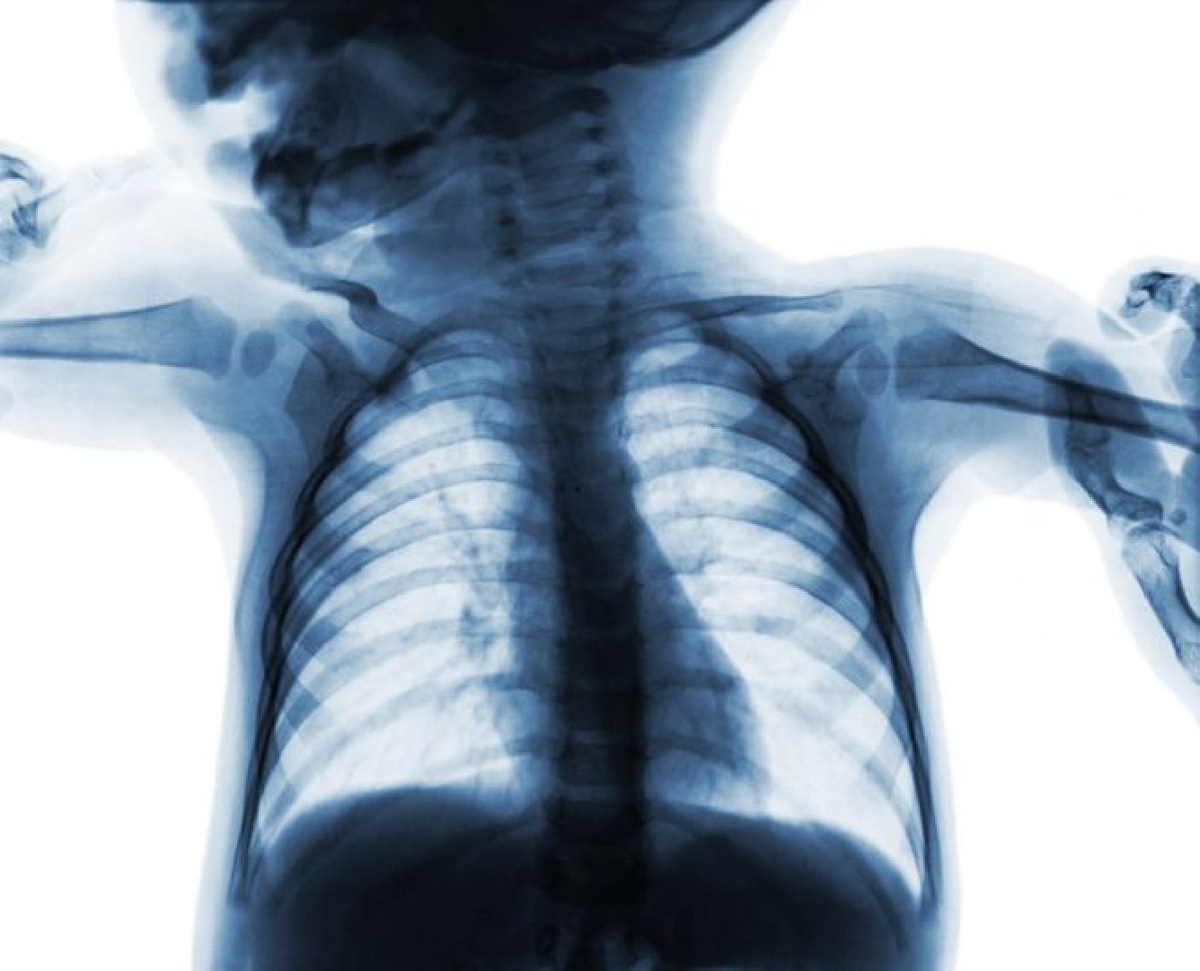

В Челябинской областной детской клинической больнице врачи спасли десятимесячного ребёнка, который чуть не задохнулся из-за кусочка ногтя своей матери. Об этом сообщает пресс-служба ЧОДКБ.

Младенец поступил в медучреждение с жёстким дыханием и хрипами. Мама предположила, что малыш подавился собачьим кормом. Медики провели обследование и обнаружили в голосовой щели плотное инородное тело, похожее на кость.

Оно перекрывало просвет дыхательных путей почти полностью. Извлечь предмет гибким эндоскопом не удалось — инструменты соскальзывали с гладкой поверхности. Тогда врачи решили провести ригидную бронхоскопию.

С помощью жёстких щипцов они прошли через голосовую щель и успешно удалили помеху. Инородным телом оказался фрагмент нарощенного ногтя. После операции ребёнок провёл ночь в реанимации, а затем его перевели в обычную палату для наблюдения.